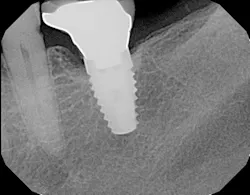

Peri-implantitis has been defined as an inflammatory process that affects the tissues around an osseointegrated implant in function and, like periodontitis, results in loss of supporting bone6 (Figs. 3 and 3a). The prevalence of peri-implantitis has been shown in some studies to range from 11% to as high as 47% of implant sites analyzed.(16) Most literature reviews agree that once bone loss has occurred around an implant, nonsurgical therapy is not as effective as surgical treatment.(17) Surgical intervention by the dentist or specialist includes raising a full thickness flap around the affected dental implant in order to completely expose the dental implant surface (Fig. 4). Mechanical debridement with hand and high-speed instrumentation as well as irrigation with various medicaments is advocated in order to detoxify the implant surface and alleviate bacterial contamination. After decontamination, the flap can be apically or coronally positioned. In addition, various regenerative technologies, including bone and soft-tissue grafts, growth factors, and barrier membranes have been used to rebuild lost tissue support around the dental implant (Figs. 5 and 5a). Different methods of guided bone regeneration around implants affected with peri-implantitis were demonstrated, and the results have been shown to be stable for a follow-up period of up to seven years.(18) That being said, no gold standard of peri-implant disease has been documented and "available evidence does not allow specific recommendations for the therapy of peri-implantitis."(19)